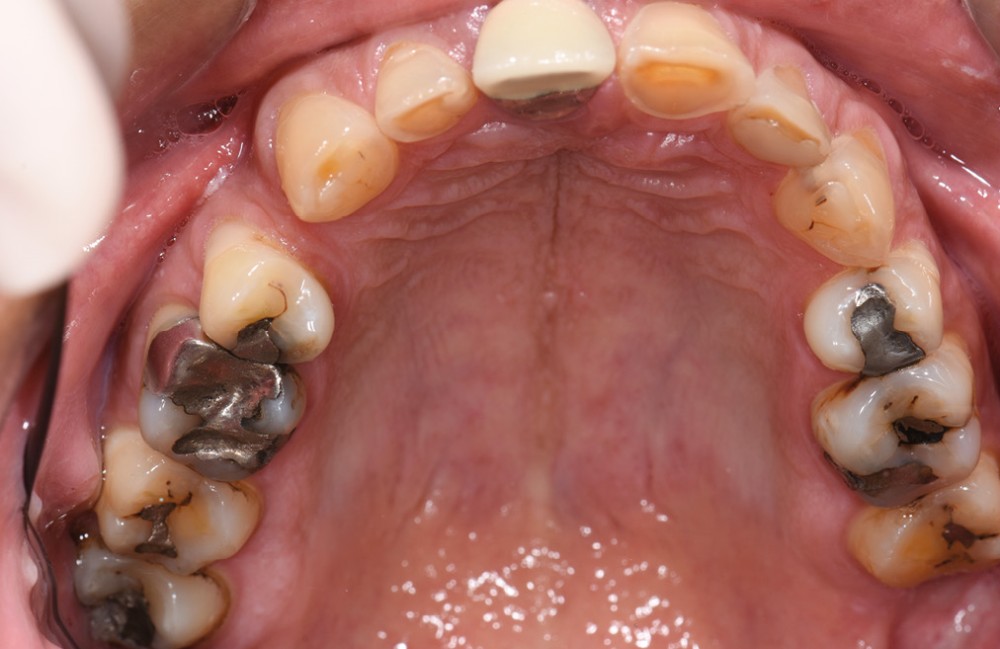

L’usure dentaire est de plus en plus fréquente au sein de nos cabinets. Nos patients y sont sujets de par leur alimentation parfois plus acide, leur mode de vie souvent plus stressant, et également une hygiène qui s’améliore et des dents qui vieillissent davantage.

L’étiologie de cette usure est multifactorielle, revêtant une composante de type attrition (usure par contact dento-

dentaire), une composante abrasive avec un brossage traumatique et, en dernier lieu, une légère composante tribo-érosive de par une pratique importante de sport avec gel et boisson acide (fig. 1-4) [1].